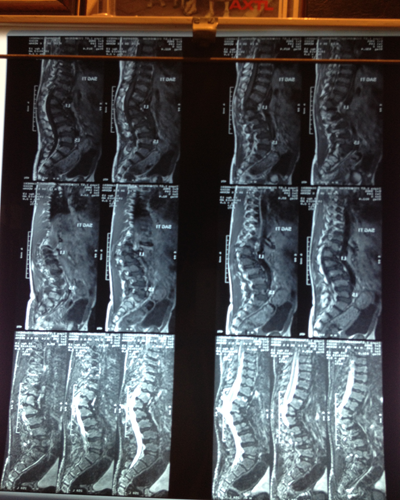

Degenerative Disc Disease (DDD) of the spine is caused by progressive degeneration of the spinal discs. Spinal discs are soft, compressible discs that separate the interlocking bones (vertebrae) that make up the spine. The discs act as shock absorbers for the spine, allowing it to flex, bend, and twist. Degenerative disc disease can take place throughout the spine, but it most often occurs in the discs in the lower back (lumbar region) and the neck (cervical region).

Degenerative disc disease is caused by progressive degeneration of the spinal discs. World over Degenerative disc disease s is one of the main causes of musculoskeletal disorder and Lifetime incidence of DDD is reported to be 60-90% with annual incidence of 5%. Each year, 14.3% of new patient visits to primary care physicians are for DDD, and nearly 13 million physician visits are related to complaints of chronic DDD. Current management of DDD is only for temporary symptomatic relief and neither addresses the cause of disease nor reverses the disease process. Moreover the adverse effects of medication and complication of interventions along with presence of other co-morbidities limit their use.